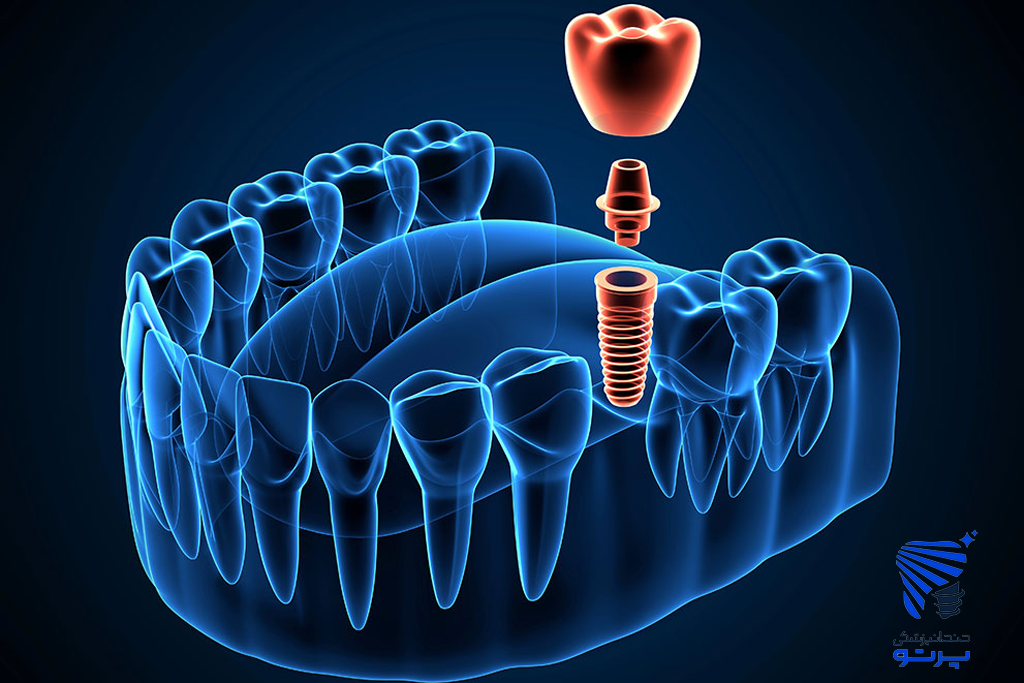

دندانپزشکی پرتو یکی از مراکز معتبر در غرب تهران است که خدمات تخصصی ترمیمی، زیبایی، روکش دندان، ایمپلنت، لمینت و عصب کشی را با تجهیزات به روز ارائه می دهد.